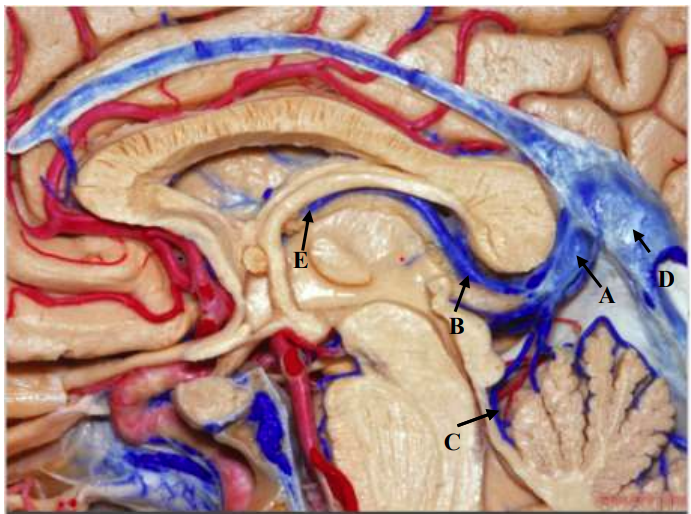

Qual seta aponta para a Veia de Galeno?

Qual seta aponta para a Fímbria do Fórnix?